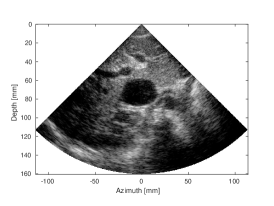

| (d) SLT | (e) MLT, (Tukey, =0.5) | (f) MLT, CNN | |

| CNR=1.41, CR=-27.37dB | CNR=1.19, CR=-12.99dB | CNR=1.41, CR=-25.96dB |